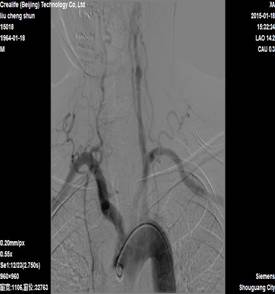

双重抗血小板,并查颈部+颅脑CTA,结果示右侧颈动脉及右侧椎动脉闭塞,左侧颈内动脉起始端闭塞,左侧椎动脉起始端重度狭窄。

图1 右侧颈动脉及右侧椎动脉闭塞,左侧颈内动脉起始端闭塞,左侧椎动脉起始端重度狭窄